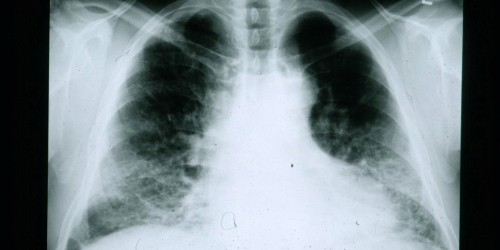

Interstitial lung disease, is the same condition as idiopathic pulmonary fibrosis, just the names are different. Some other terms for the same condition are connective tissue or autoimmune disease-related pulmonary fibrosis. Sometimes, interstitial lung disease is called hypersensitivity pneumonitis, or sarcoidosis, as well as many others. The most common symptoms of interstitial lung disease are shortness of breath with exercise and a non-productive cough. These symptoms are generally slowly progressive, although rapid worsening can also occur in some patients. Some people also may have a fever, weight loss, fatigue, muscle and joint pain, and abnormal chest sounds. It is depending upon the cause of patient’s interstitial lung disease. In this disease, the tissue in the lungs becomes inflamed or sometimes even scarred. I think you could reach conclusion until now, that progression of interstitial lung disease varies from disease to disease and from person to person. It is important to determine the specific form of disease in each patient, because what happens over time and the treatment may differ depending on the cause. you should also know that each person responds differently to treatment and close monitoring during treatment is important.